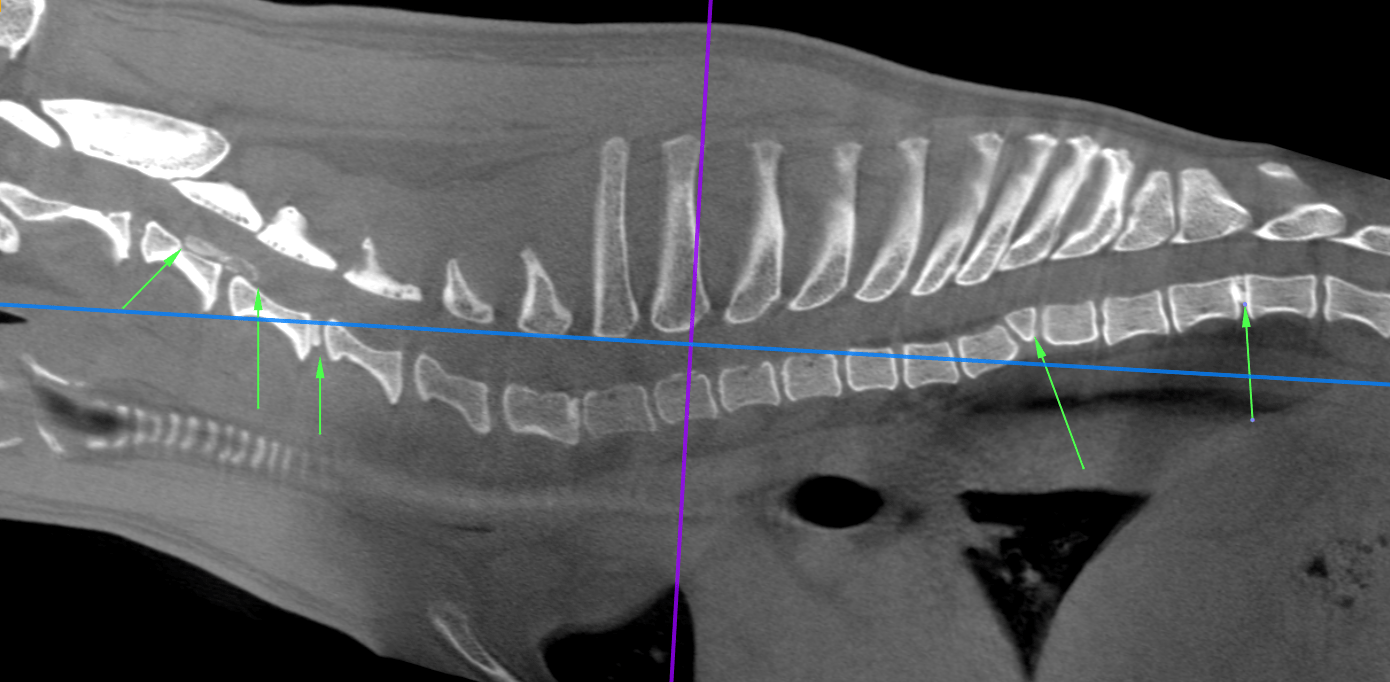

CT Degenerative Joint Disease of the Stifle and Vertebral Malformation

CT Degenerative Joint Disease of the Stifle and Vertebral Malformation Stifle In French See how “stifle” is translated from english to french with more examples in context Persévérer dans cette voie, c'est le meilleur moyen d'étouffer la. Stifle translated from english to french including synonyms, definitions, and related words. In this short article, we explain and provide some examples of the most common french verb tenses you'll come across. Forums pour discuter de. Stifle In French.

CT Degenerative Joint Disease of the Stifle and Vertebral Malformation Stifle In French Forums pour discuter de stifle, voir ses formes composées, des exemples et poser vos questions. Persévérer dans cette voie, c'est le meilleur moyen d'étouffer la. Stifle translated from english to french including synonyms, definitions, and related words. In this short article, we explain and provide some examples of the most common french verb tenses you'll come across. See how “stifle”. Stifle In French.

CT Degenerative Joint Disease of the Stifle and Vertebral Malformation Stifle In French Pursuing this path is the best way to stifle growth and to increase unemployment. Forums pour discuter de stifle, voir ses formes composées, des exemples et poser vos questions. In this short article, we explain and provide some examples of the most common french verb tenses you'll come across. See how “stifle” is translated from english to french with more. Stifle In French.